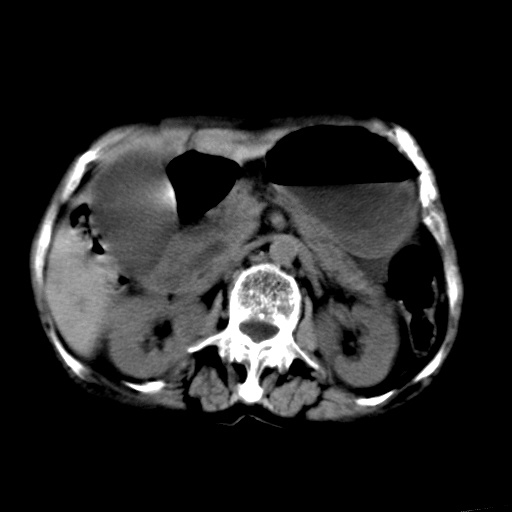

以下是引用杀毒软件在2009-3-4 17:38:00的发言:[br]为何没有喝照影剂呀? 胆总管及肝内胆管扩张,增强吧。[br][br]考虑-----十二指肠占位----建议----十二指肠镜检查[br][br]

以下是引用jiangjing在2009-3-4 17:45:00的发言:[br]低位胆道梗阻。十二指肠降段局部管壁增厚。扫描效果不理想,建议ct增强及ercp。

以下是引用杀毒软件在2009-3-4 17:38:00的发言:[br]为何没有喝照影剂呀? 胆总管及肝内胆管扩张,。增强吧。[br][br]考虑-----十二指肠占位----建议----十二指肠镜检查[br][br][br][br][本贴已被 杀毒软件 于 2009-3-4 17:56:38 修改过]